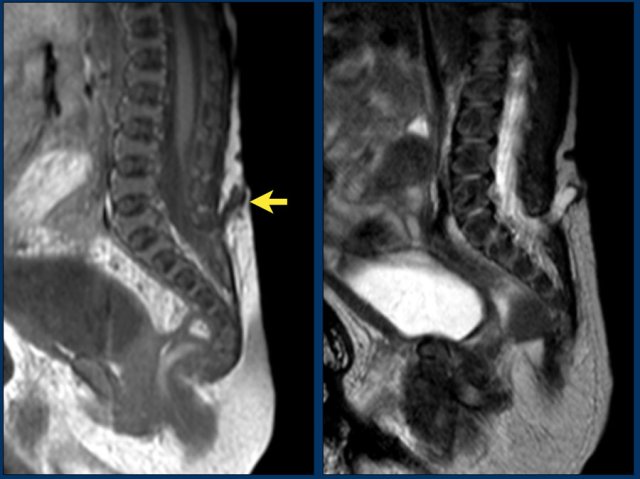

Newborn girl with a cloacal malformation.

The conus medullaris is at L5.

No lipoma visible.

Findings were confirmed at MR imaging which was acquired at the age of 9 months.

Continue with the MR.

MR image at the age of 9 months.

The conus medullaris is now seen at L4.